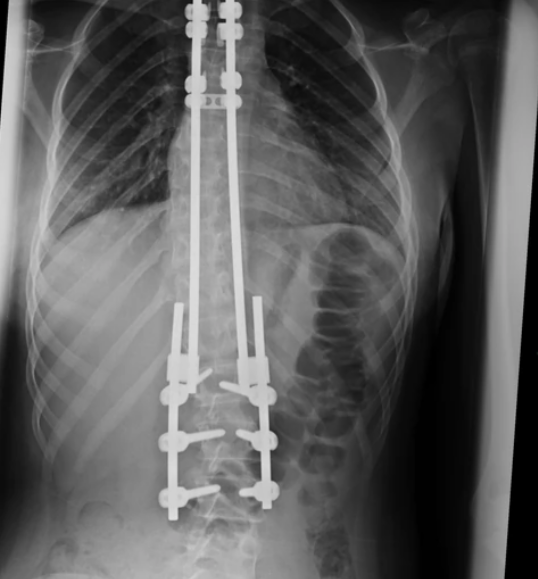

U toj ustanovi kažu da su paralelno sa razvojem spinalne hirurgije tamo usvajane i nove metode rješavanja neuromuskularnih skolioza u vidu bipolarne tehnike koju je opisao i uveo dr Lotfi Miladi iz Necker Klinike u Parizu koji je takođe posjetio novosadski Institut kako bi se uvjerio da ima dovoljno kapaciteta i stručan kadar za ovakve zahvate. U skladu sa tim, Institut je bio i domaćin prvog međunarodnog Vebinara iz spinalne hirurgije.

Na Institutu za zdravstvenu zaštitu djece i omladine Vojvodine, prvi put je izvedena neinvazivna hirurška metoda uz pomoć svjetskih stručnjaka za spinalnu hirurgiju a sada je veoma uspješno obavljaju naši hirurzi – ortopedi uz asistenciju kolega iz Španije i Francuske i planirano je da se uskoro u toj vojvođanskoj ustanovi potpuno besplatno operišu sva djeca iz Srbije koja boluju od te smrtonosne bolesti.

Ljekar koji je pod mentorstvom stranih stručnjaka među prvima u Srbiji počeo da izvodi ovakve vrste operacija bio je dr Vladimir Đan iz Instituta za zdravstvenu zaštitu djece i omladine Vojvodine koji u izjavi objašnjava da deformiteti kičmenog stuba nisu samo estetski problem, već da oni predstavljaju ozbiljno zdravstveno stanje koje može da dovede do komplikacija koje su opasne po život ukoliko se na vrijeme adekvatno ne liječe.

“Postoji više vrsta skolioza prema uzroku nastajanja, a za pedijatrijsku populaciju najznačajnije su idiopatske, urođene i neuromuskularne skolioze. Traumatske i sindromske skolioze su veoma rijetke u ovom uzrastu. Prema epidemiološkim podacima koje su dostupne u literaturi, idopatskih skolioza ima oko 2-3 procenta, dok onih koji imaju značajnu krivinu (preko 30 stepeni) od 0,1 do 0,3 slučaja na 100 stanovnika. Kada se epidemiološki podaci za idiopatsku skoliozu koja je najčešća primjene na demografsku sliku naše pokrajine dobijemo da prosečno dijve do tri hiljade djece u uzrastu od 10 do 15 godina imaju postavljenu dijagnozu skolioze a od toga 200-300 imaju značajnu krivinu koja mora da se adekvatno prati i u jednom momentu reagije. Razlog razmatranja ove grupe pacijenata leži u tome što su ova djeca sem deformiteta kičmenog stuba uglavnom zdrava djeca i predstavljali bi radno sposobno stanovništvo nakon izlječenja”, kaže dr Đan.

Sa druge strane, kako kaže, neuromuskularne skolioze su velik problem i hirurški izazov jer su ta djeca izuzetno lošeg opšteg stanja sa progresijom osnovne bolesti. Prema literaturnim podacima incidenca je dva slučaja na 1.000 živorođene djece.